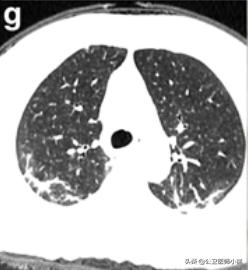

根据感染的不同程度累积一个或多个肺叶

肺部感染涉及多个肺叶-1

肺部感染涉及多个肺叶-2

肺部感染涉及多个肺叶-3

当涉及到一个或多个肺叶,肺功能的影响并不严重时,呼吸急促和呼吸困难的症状也并不严重。随着病情的发展,肺部实变开始吸收,密度降低逐渐变成毛玻璃样的混浊,像融化的糖。